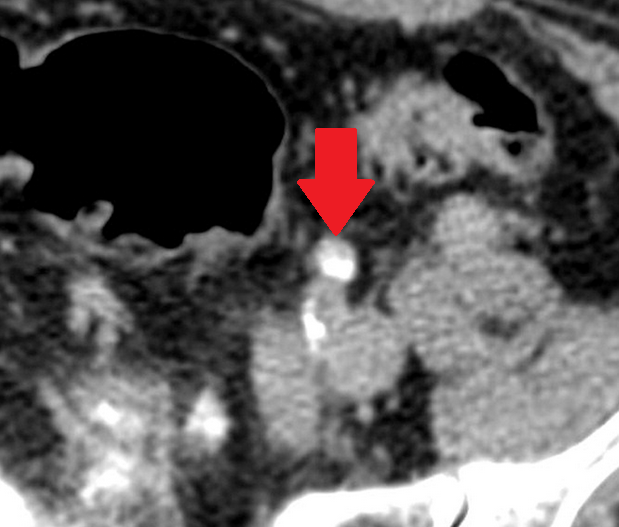

Διάταση αριστερού ουρητήρα λόγω παρουσίας πιθανής εμφύτευσης (Ευγενική παραχώρηση Dr. V. Penopoulos)